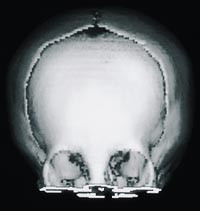

Cerebral CT med tredimensjonal rekonstruksjon viste lukket metopicasutur og trigonocefalistigmata (fig 2). For øvrig var det normalt store ventrikler og upåfallende intrakraniale forhold.

Cerebral CT med tredimensjonal rekonstruksjon viste lukket metopicasutur og trigonocefalistigmata. For øvrig var det normalt store ventrikler og upåfallende intrakraniale forhold.